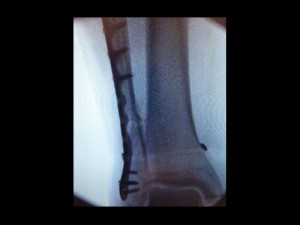

After receiving x-rays following the Gothenburg show that confirmed a broken fibula, the band cancelled dates at the Pinkpop Festival in the Netherlands (6/14) and St. Gallen, Switzerland (6/16). Grohl flew to London for further x-rays and an MRI followed by an operation on Monday (6/15) in which a plate held in place by six screws was attached to the bone.